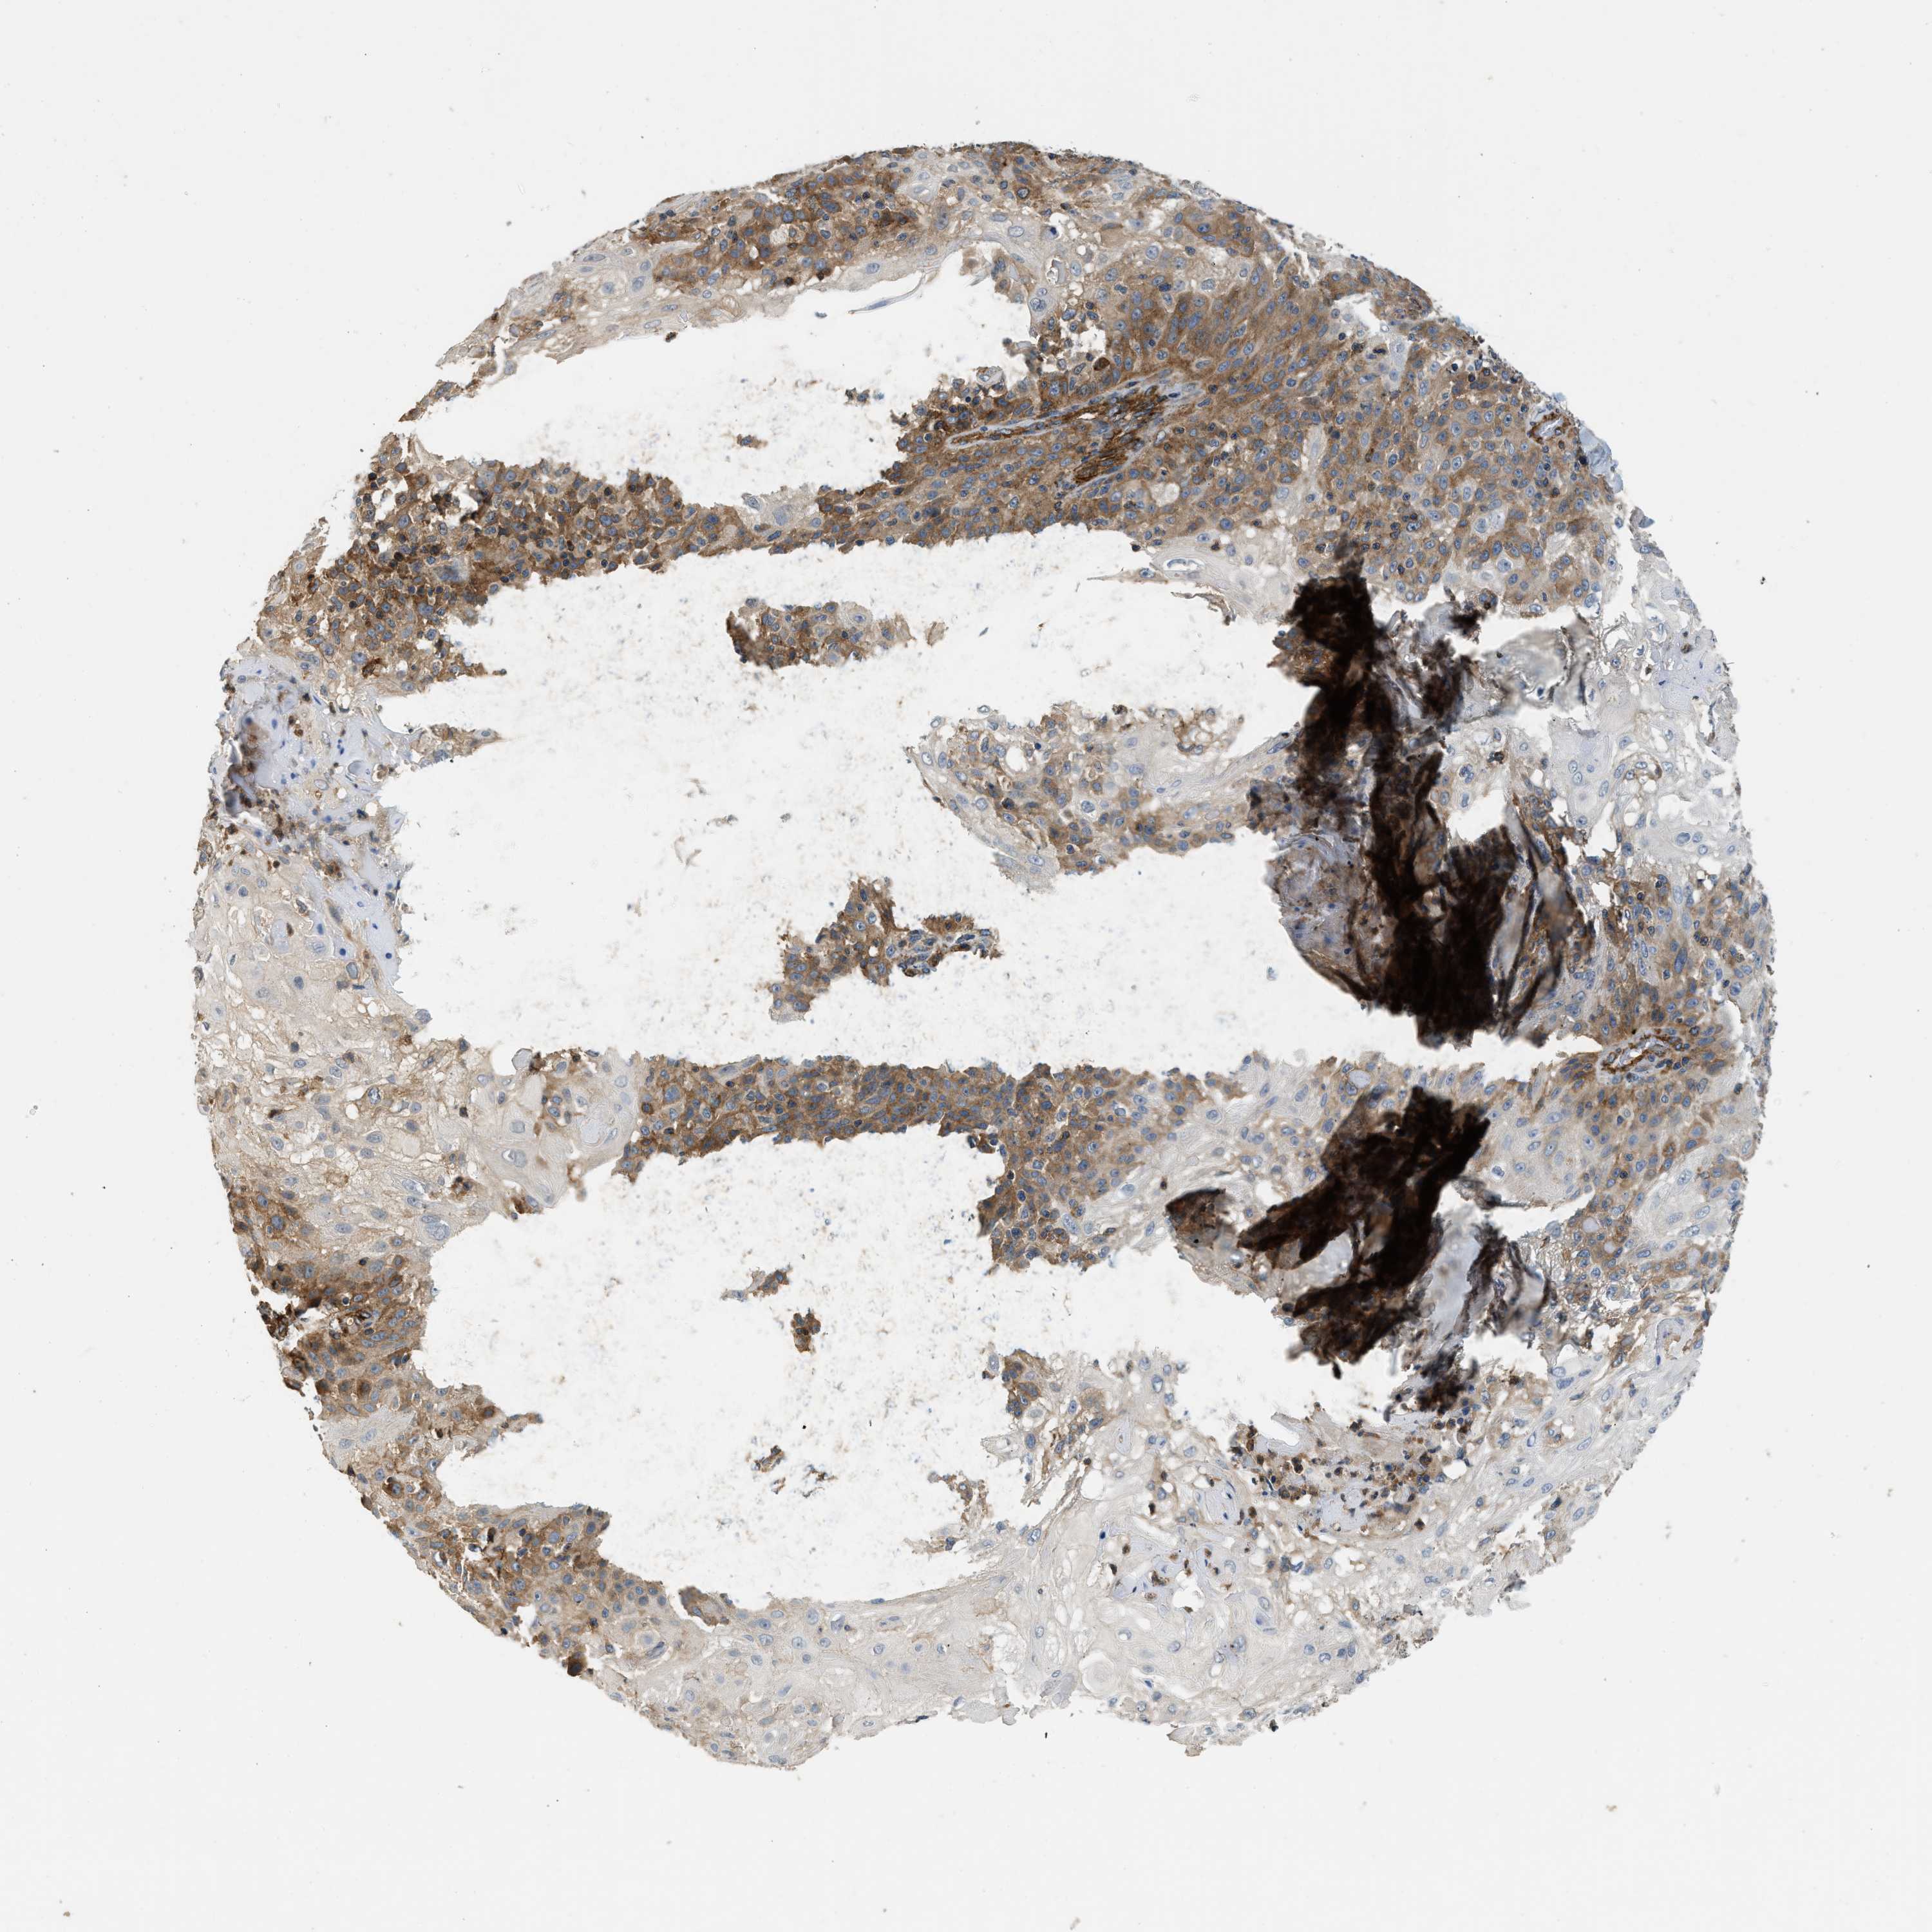

SKIN CANCER - Protein expressioni

A mouse-over function shows sample information and annotation data. Click on an image to view it in a full screen mode. Samples can be filtered based on level of antibody staining by selecting one or several of the following categories: high, medium, low and not detected. The assay and annotation is described here.

Antibody stainingi

Antibody staining in the annotated cell types in the current human tissue is reported as not detected, low, medium, or high, based on conventional immunohistochemistry profiling in selected tissues. This score is based on the combination of the staining intensity and fraction of stained cells.

Each image is clickable and will lead to virtual microscopy that enables deeper exploration of all samples and also displays staining intensity scores, fraction scores and subcellular localization as well as patient and tissue information for each sample.

Antibody HPA013606

Antibody HPA017964

Antibody CAB015334

Antibody CAB016402

Staining

High

Medium

Low

Not detected

Intensity

Strong

Moderate

Weak

Negative

Quantity

>75%

75%-25%

<25%

None

Location

Nuclear

Cytoplasmic/membranous

Cytoplasmic/membranous,nuclear

Squamous cell carcinoma in situ, NOS

Squamous cell carcinoma, NOS

Squamous cell carcinoma, metastatic, NOS

Basal cell carcinoma

Adnexal tumor, benign